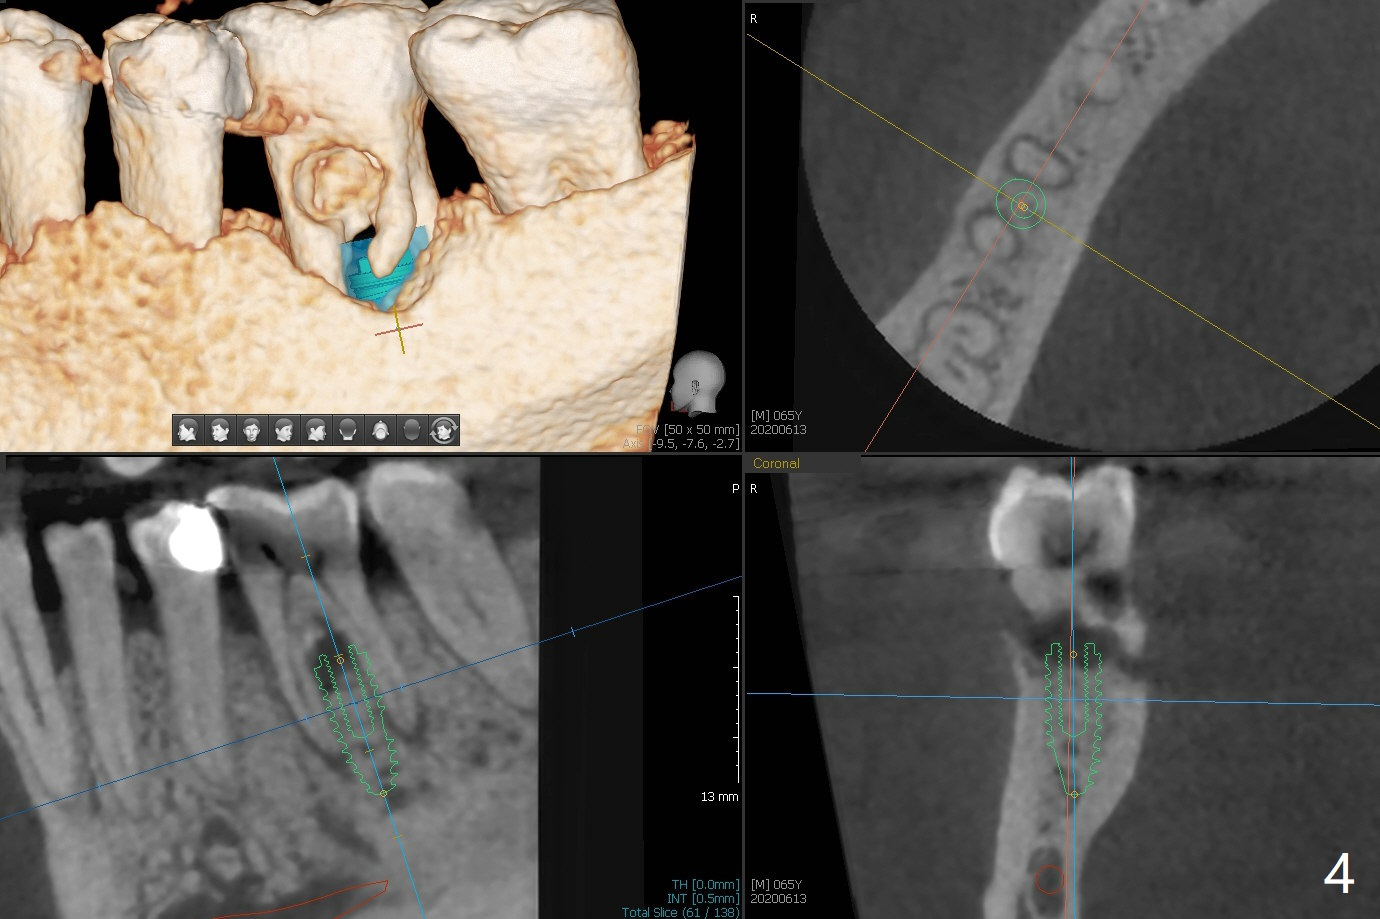

A 65-year-old man has nocturnal pain associated with #30 lingual furca caries and gingival recession (Fig.1,2). PRF (x2) and sticky bone will be used to repair the lingual soft and hard tissue defects. CT shows the submandibular fossa (Fig.3 <), dictating a short implant 10 mm, Fig.4). To place the implant in the septum (Fig.3 S), the coronal portion of the tooth is removed (Fig.5 black area) so that the roots are able to keep the osteotomy without deviation (Fig.6 red arrow). It is possible to place the implant in a trajectory mesiodistally (Fig.7 in fact after root extraction (arrows)). To prevent buccolingual deviation, a small implant (4 mm in diameter) is designed so that it will NOT touch the buccal (B in Fig.8) or lingual (L) plates. The bone density of the cortex and medulla is 2000 and 1400 units, respectively. To reduce the chance of implant fracture because of the narrow diameter in function, an implant with Titanium V will be used.